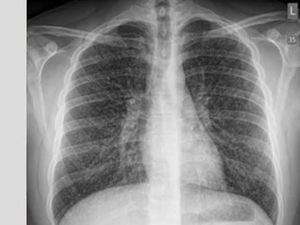

Apakah Vape Berbahaya untuk Paru-paru? Begini Faktanya

Beberapa orang meyakini, vape adalah solusi alternatif untuk orang yang ingin berhenti merokok konvensional. Lantas, apakah vape berbahaya untuk paru-paru?